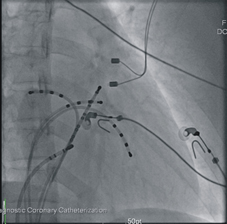

手術前需禁食八小時,手術時主治醫師在林小姐的雙側鼠蹊部打局部麻醉,打針找到股靜脈插入導管(如:圖二) ,直徑粗細如同原子筆心,接著在X光透視下經鼠蹊部放入數根細長的電極導管(如:圖三),藉由電極導管在心臟內誘發來確定心臟異常傳導的位置,予以燒灼,在燒灼完畢後,再反覆用電極導管做誘發測試,看有無殘存的異常傳導路徑。手術完畢,就在恢復室幫林小姐拔除身上的電極導管予以加壓止血,在確定林小姐的意識狀況清醒與生命跡象穩定就轉回普通病房。在病房林小姐仍需平躺6至8小時,期間如需解大小便,需要家屬協助使用便盆不可下床,以免傷口裂開出血。

圖二、打針找到股靜脈插入導管

圖三 、在X光透視下經鼠蹊部放入數根細長的電極導管